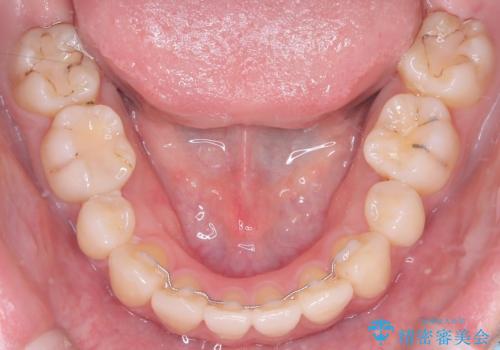

治療の結果、長年のコンプレックスであった口元の突出感が大幅に解消され、横顔のライン(Eライン)が美しく改善しました。機能的な咬み合わせを確立すると同時に、患者様が望んでいた審美的な口元を獲得していただけました。

今回の矯正治療では、口元の突出感を解消するためのスペースを確保するため、計画通り上下左右4本の小臼歯を抜歯しました。装置には、確実な歯の移動と細やかな調整が可能なワイヤー矯正を採用。抜歯によってできたスペースを最大限に利用し、前歯を奥へ、そして垂直的に慎重に移動させました。